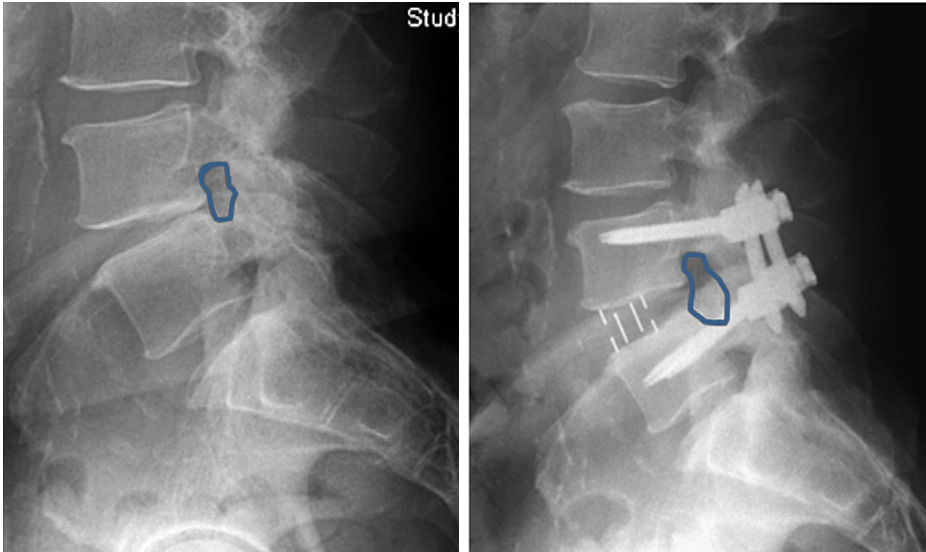

Posteriormente con la ayuda de un separador especial (Fig 3) y de instrumentos específicos, se reseca el disco intervertebral con el fin de colocar cajas rellenas de injerto en lugar de los discos que se han quitado y conseguir con esto diferentes funciones una separación de las vertebrales y por tanto un aumento del canal espinal y de los forámenes por los que salen las estructuras nerviosas, con lo que se consigue una descompresión de los elementos nerviosos (descompresión indirecta) (Fig 4).

También se pueden corregir deformidades tanto en el plano frontal como en el lateral según el tipo de cajas que se implanten.

Con una caja aislada no se consigue suficiente estabilidad y se recomienda la colocación de un sistema de sujeción adicional con tornillos (Fig 5) desde la vía lateral o una fijación posterior, pudiendo ser esta percutánea y por tanto menos cruenta (Fig 6).